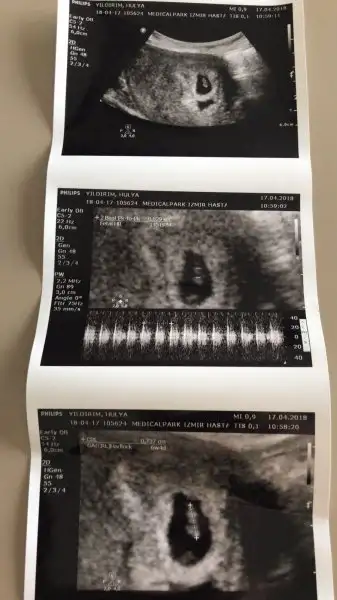

Teşekkür ederim biz olduk 12+2 nub yorumlayabiliyor musun?Kız gibi cnm

Onu tam secemiyorum yani anlamiyorum canım bu teoriyi bile pek bilmiyorum kendimce yorum yapıyorum canımTeşekkür ederim biz olduk 12+2 nub yorumlayabiliyor musun?

Ramzi teorisine göre ( bilimsel bir araştırma sonucuymuş ve %85 doğruluğu varmış). İlk 6-8 haftalık ultrason görüntüsüne göre bebeğin kesenin içersinde soldan ya da sağdan girişine göre cinsiyet tahmini yapılıyor. Bilimsel olunca tecrübeli annelerimiz yada anne adaylarımızdan yardım istiyoruz. Doğruluğu var mı öğrenmek adına :) Bizleri aydınlatırsanız çok seviniriz. bu teorieye göre;

Vajinal muayeneyle bakıldıysa eğer;

Sağdan girmiş gözüküyosa aslında solmuş ve ERKEK,

Soldan girmiş gözüküyosa aslında sağmış ve KIZ ,

Karından bakıldıysa eğer,

Soldan girmiş gözüküyosa gerçektede solmuş ve ERKEK,

Sağdan girmiş gözüküyosa gerçekte de sağmış ve KIZ,